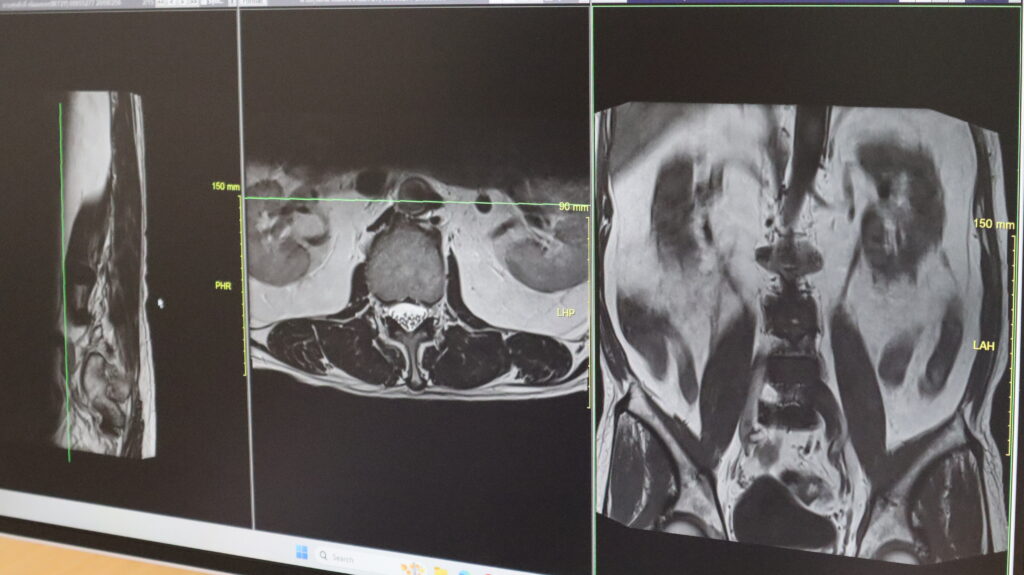

วิทยการการรักษาที่ว่านี้คือ เอนโดสปาย (EndoSpine): ผ่าตัดเฉพาะจุด เห็นชัด ปลอดภัยกว่าเดิม เทคโนโลยี EndoSpine คือการผ่าตัดผ่านกล้องชนิดพิเศษที่ออกแบบมาเฉพาะสำหรับกระดูกสันหลัง ช่วยให้แพทย์สามารถมองเห็นจุดที่กดทับเส้นประสาทได้อย่างชัดเจน และผ่าตัดเฉพาะส่วนที่จำเป็นโดยไม่กระทบต่อโครงสร้างรอบข้าง ข้อดีคือเราแก้ไขเฉพาะจุด ไม่ต้องรื้อโครงสร้างทั้งหมด แผลเล็ก เสียเลือดน้อย ความเสี่ยงต่ำ และฟื้นตัวได้เร็ว”

ปัจจุบัน Endospine Center ศูนย์กระดูกสันหลังและข้อ รพ วัฒนา อุดรธานี ถือเป็นโรงพยาบาลเอกชนแห่งเดียวในภาคอีสาน ที่มีเทคโนโลยีกล้อง EndoSpine รุ่นใหม่ล่าสุด ซึ่งให้ภาพขยายคมชัดระดับมิลลิเมตรช่วยลดโอกาสการบาดเจ็บต่อเส้นประสาทได้อย่างมากนอกจากนี้ การผ่าตัดด้วยเทคนิคนี้ยังสามารถทำได้โดย ฉีดยาชาเฉพาะจุดผู้ป่วยบางรายสามารถ “มาเช้าเย็นกลับ” ได้โดยไม่ต้องดมยาสลบ